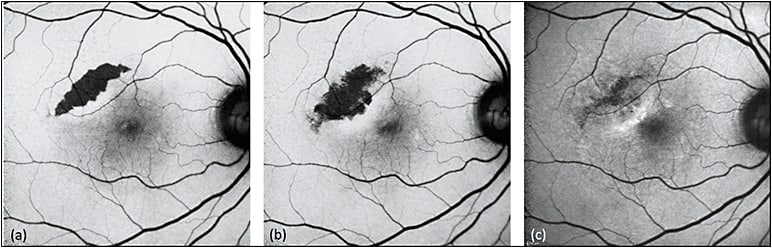

As a well-known complication of AMD, RPE tears present as a wedge- or crescent-shaped area of remarkable hypoautofluorescence with sharp, irregular borders representing the zone of denuded RPE, and adjacent hyperautofluorescence at the site of rolled retracted RPE (Figure 1). Over time, RPE tears undergo resurfacing, with recovery of autofluorescence and associated visual function occurring centripetally toward the center of the lesion (Figure 2).15-18

Figure 2. Sequential FAF of RPE tear treated with aflibercept. RPE tears (a) appear as a well-demarcated central hypoautofluorescence due to absent RPE with adjacent irregular hyperautofluorescence corresponding to the retracted edges of RPE. The patient received anti-VEGF therapy with half-dose aflibercept. Over time (b), the lesion shows evidence of remodeling and resurfacing, with centripetal recovery of autofluorescence.

COURTESY OF WOLTERS KLUWER